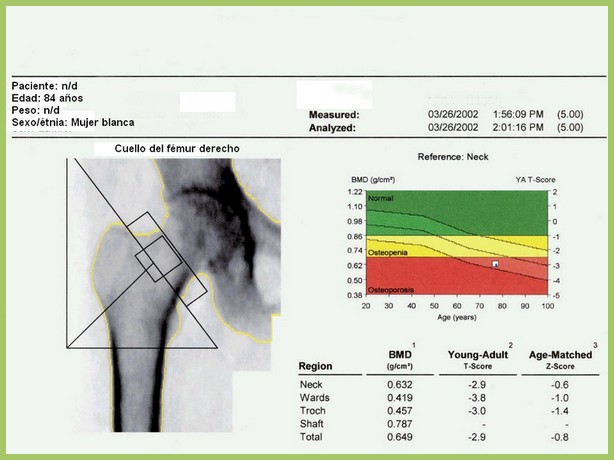

En este estudio argentino, la mitad de las densitometrías se pidieron en mujeres que no cumplían los criterios recomendados de edad o de riesgo aumentado para justificar el rastreo de osteoporosis. Salud Colectiva, octubre de 2016

Una revisión sistemática de los umbrales de intervención basados en la herramienta FRAX para la estimación del riesgo de fractura. Archives of Osteoporosis, 27 de julio de 2016